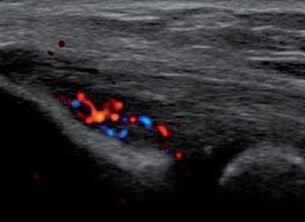

En mode Doppler

En cas de tendinopathie calcanéenne, le Doppler puissance objective la prolifération vasculaire sous forme d’hyper-signal Doppler intratendineux ou péri-enthésique, c’est-à-dire à moins de deux mm de son insertion sur la corticale osseuse (fig. 3). Le Doppler puissance a un intérêt dans le suivi des lésions, du processus de réparation et de néovascularisation, puis de cicatrisation et de guérison.25